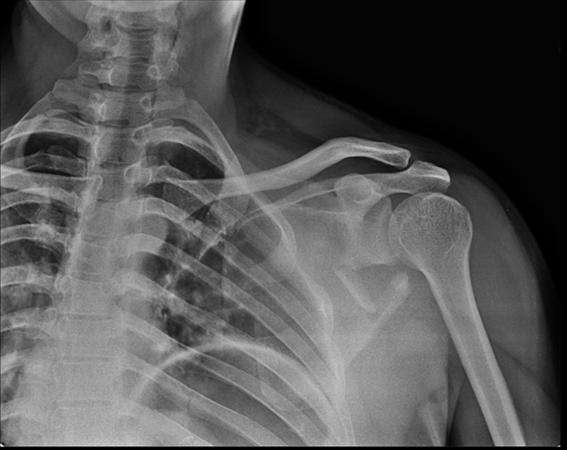

Scapula Fractures